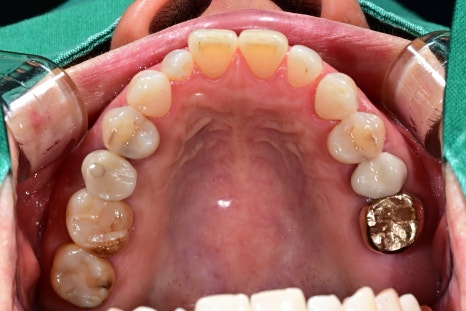

③ Implant placement (screw insertion)

This is performed under local anesthesia and finishes in a relatively short time.

Patients often say, “It ended faster than I expected.”

In this case as well, the surgery to place implants in the positions of the two molars

was completed stably.

⑤ Fabrication and placement of the final tooth (crown)

After recovery, an impression is taken with an intraoral scanner

to make a custom crown.

Seoul Oue Dental Hospital has an in-house dental technician,

which is characterized by fast and precise fabrication and modifications.